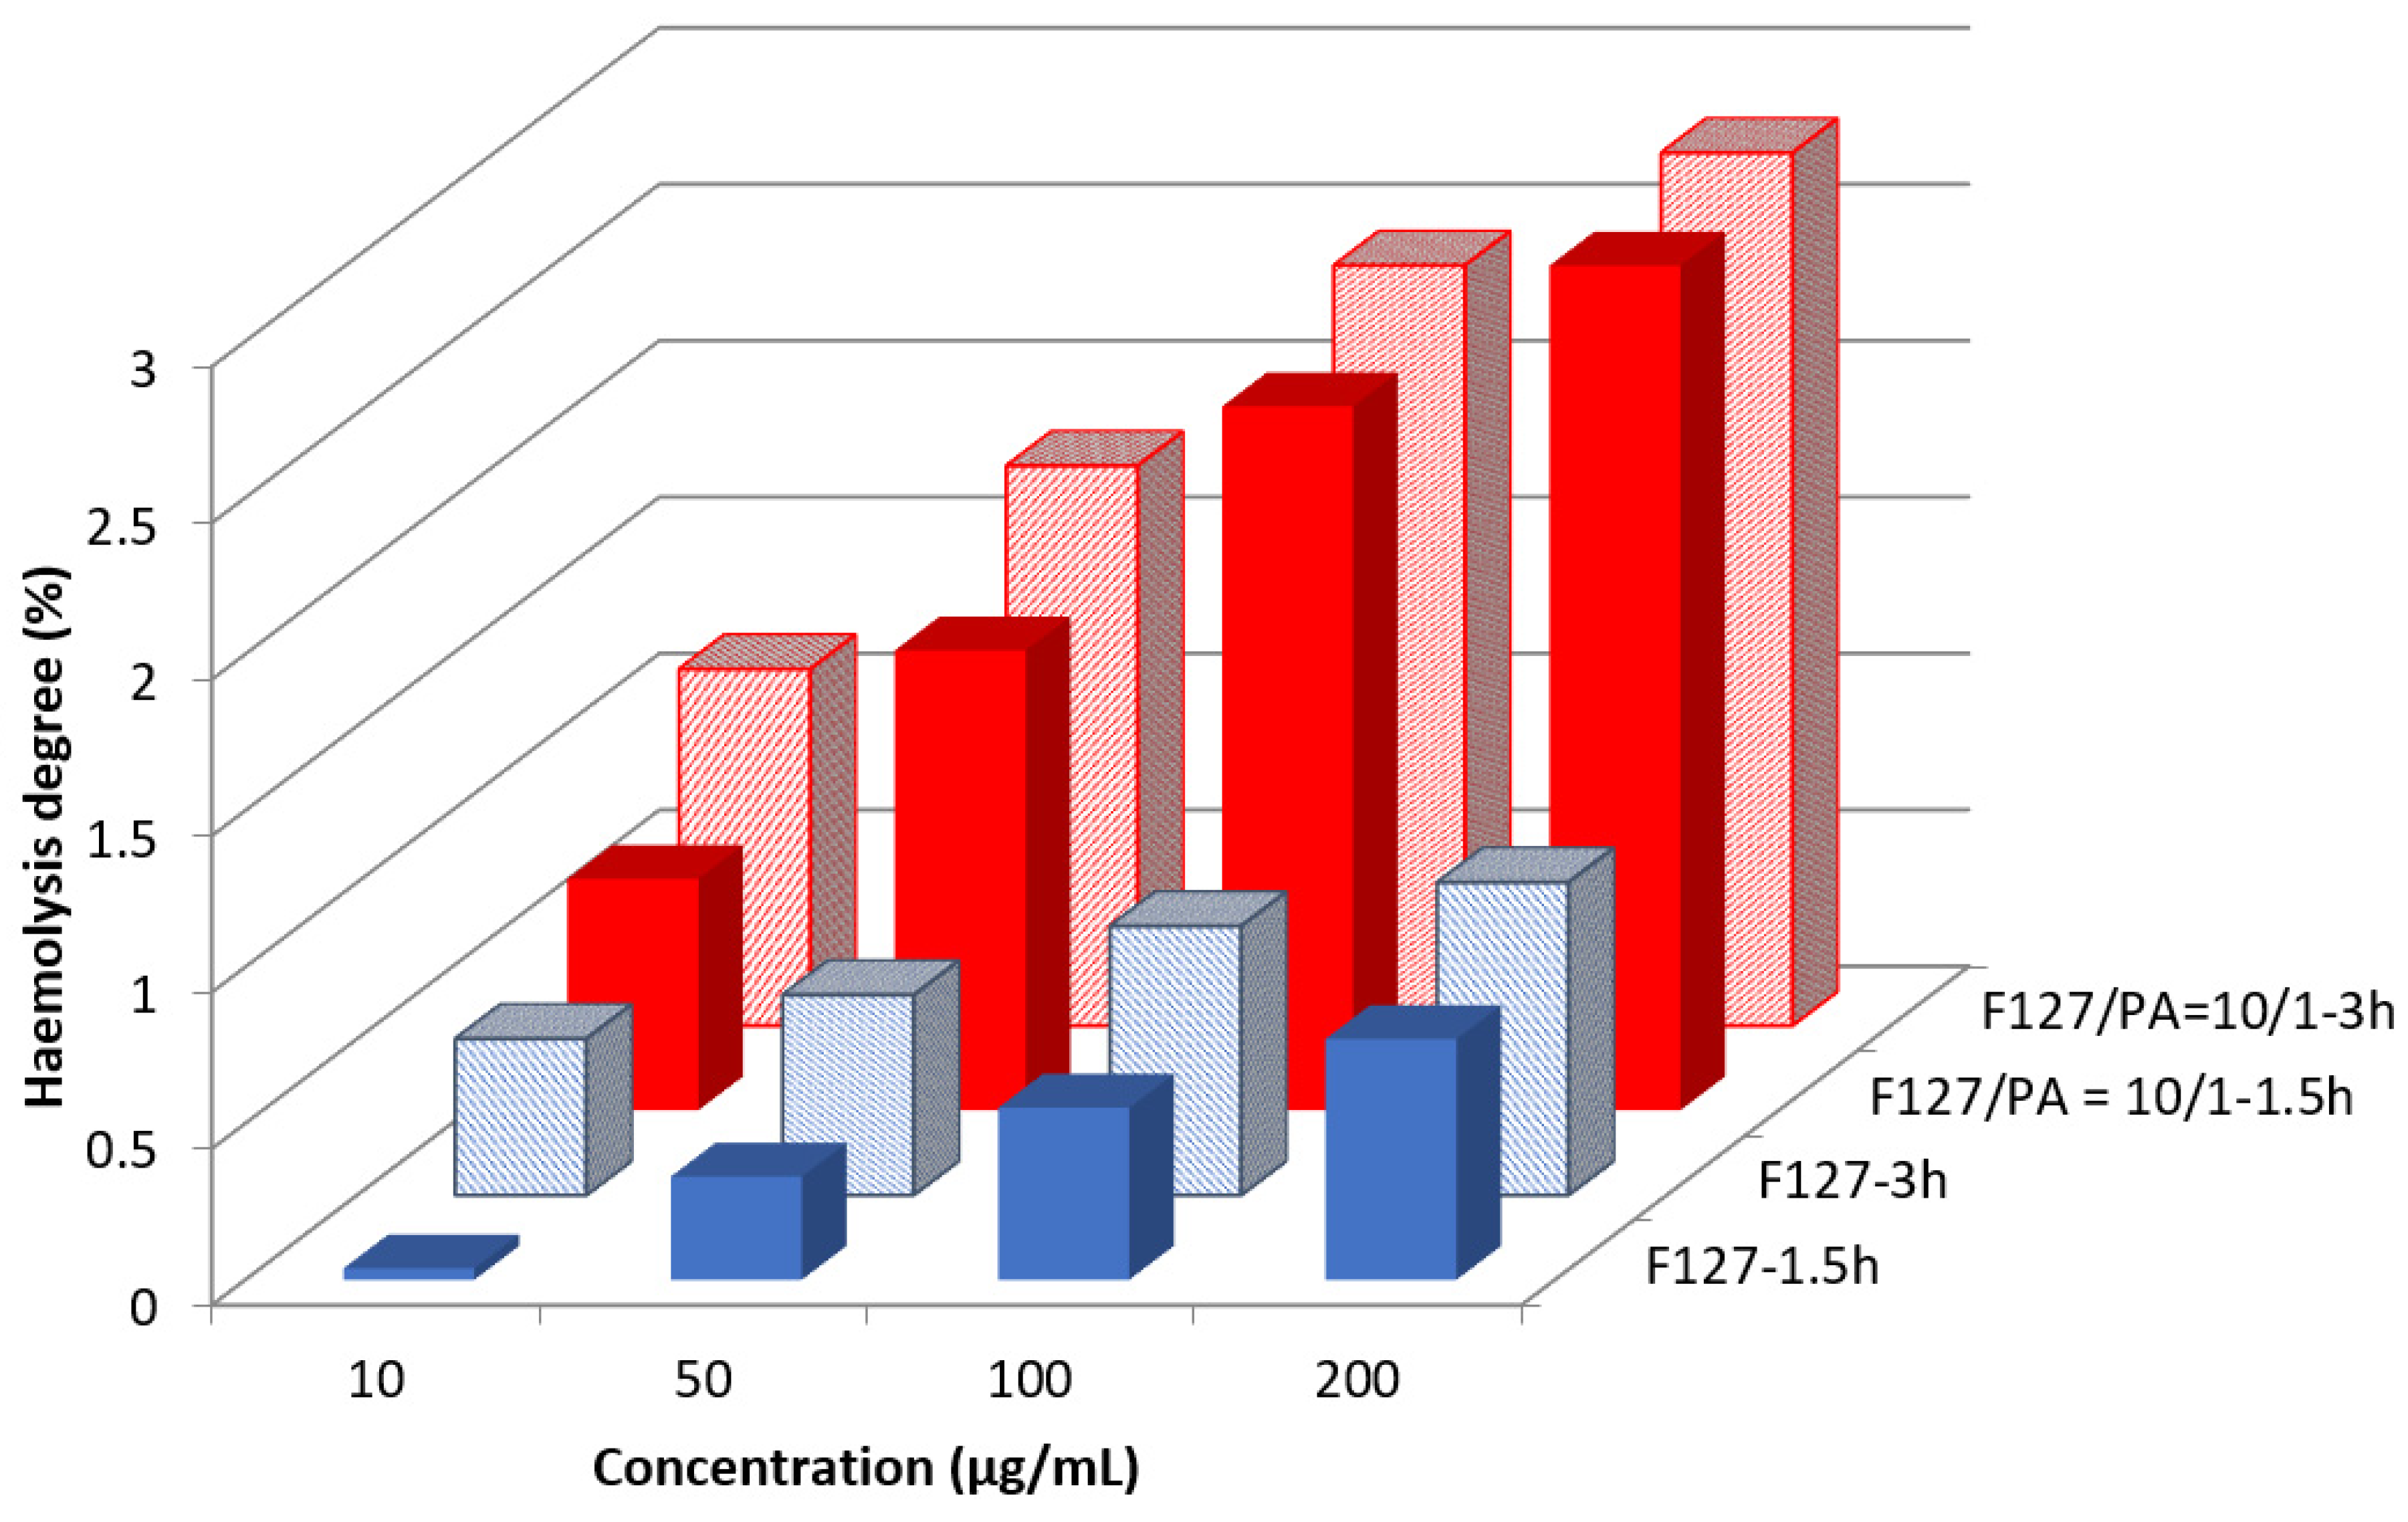

3.3. Assessment of the Haemolysis Degree